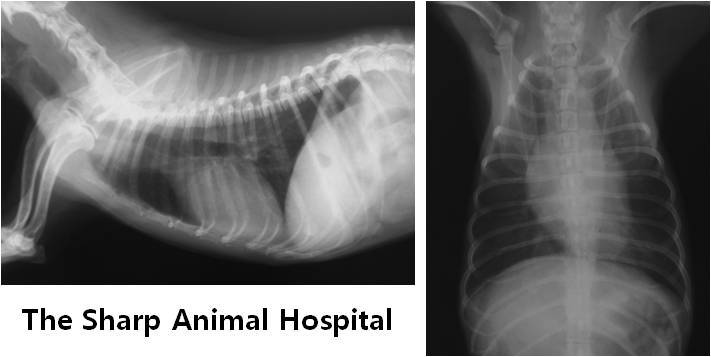

24 시간 동안 집중적인 산소 처치를 받게 된 후 호흡이 많이 좋아져서

다음날 흉부 방사선 사진을 다시 촬영 하게 되었습니다.

어제의 사진과 달리 하얗게 변해 있던 폐의 부분이 많이 검게 변한 것을 확인 할 수 있었습니다.

그쪽으로 생겼던 폐 부종이 많이 사라졌다는 뜻이지요..